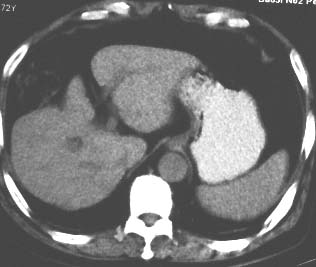

男 56 腹部不舒

典型肝硬化:1、肝各叶大小的比例失常;2、肝表面明显凹凸不整,边缘变钝;3、肝实质密度一般与正常肝无明显改变;4、肝裂增宽;5、门静脉增宽,脾静脉扩张扭曲;6、脾脏虽然不大,但不是所以肝硬化的脾脏都增大。

典型肝硬化:1、肝各叶大小的比例失常;2、肝表面明显凹凸不整,边缘变钝;3、肝实质密度一般与正常肝无明显改变,但肝右叶似可见再生结节影;4、肝裂增宽;5、门静脉增宽,脾静脉扩张扭曲;6、脾脏增大. 脾脏大小的标准有:1脾脏的左右径(大于5个肋单元) 2脾脏的宽度 3脾脏的上下径(超过肝下缘) 请参考.

典型肝硬化:1、肝各叶大小的比例失常;2、肝表面明显凹凸不整,边缘变钝;3、肝实质密度一般与正常肝无明显改变,但肝右叶似可见再生结节影;4、肝裂增宽;5、门静脉增宽,脾静脉扩张扭曲;6、脾脏增大.

典型肝硬化:1、肝各叶大小的比例失常;2、肝表面明显凹凸不整,边缘变钝;3、肝实质密度一般与正常肝无明显改变,但肉眼观察与脾胀密度低或等密度;4、肝裂增宽;5、门静脉增宽,脾静脉扩张扭曲;6、脾脏增大.

就本病例而言,楼上的战友可能有点优柔寡断。如果是先天性肝脏形态异常,那么它的密度异常就不符合了吧?仔细看,的确如多位战友所言,肝脏密度不均匀,有再生结节,考虑肝硬化应该不会出错。当然,楼上战友那样写报告是最保险的,我也会这么写,我们在实际工作中都应该学会自我保护。

肝硬化表现符合,肝脾ct值有倒置,考虑局灶性肝脂肪浸润